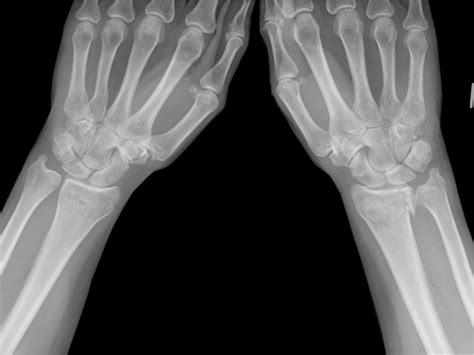

Diagnostic Procedures

Upon arriving at a medical facility, the physician will perform a physical examination followed by diagnostic imaging to confirm the Fracture Goyrand Smith. Radiographic imaging, specifically X-rays taken from multiple angles (anteroposterior and lateral views), is the gold standard for diagnosis. These images allow the doctor to determine: